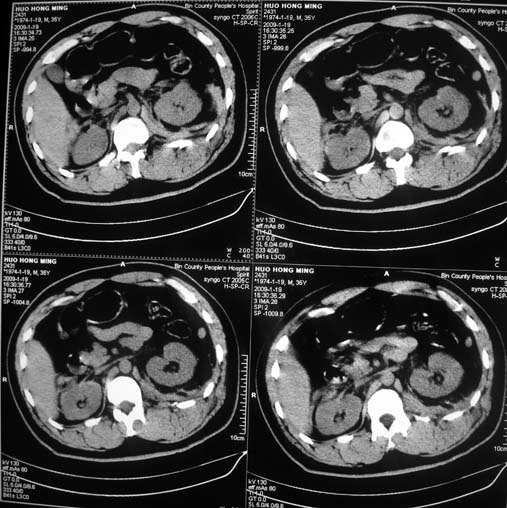

以下是引用余辉在2009-1-20 8:22:00的发言:[br]右侧肾上腺明显增大、边缘不光整,肯定有问题,结合患者病史考虑肾上腺挫伤、伴血肿形成。[br]另左肾后唇包膜下方可见局限性新月形高密度影,考虑肾包膜下出血[br]余同意楼上,建议增强排除脾破列

以下是引用随光逐影在2009-1-20 8:21:00的发言:[br]1)左侧多发肋骨及部分腰椎左侧横突骨折。2)左侧肾旁后间隙及同侧胸腔积血。3)左侧腰大肌肿胀。